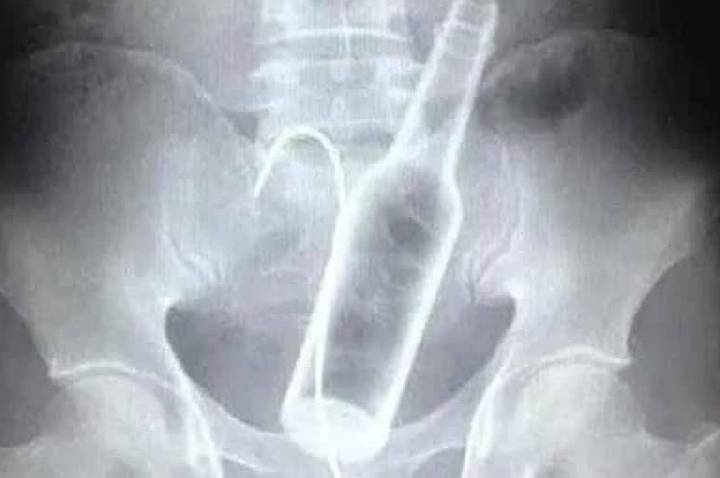

Homem é Operado Após Inserção de Garrafas no ânus

Situação extrema mobiliza profissionais de saúde e levanta debate sobre práticas...